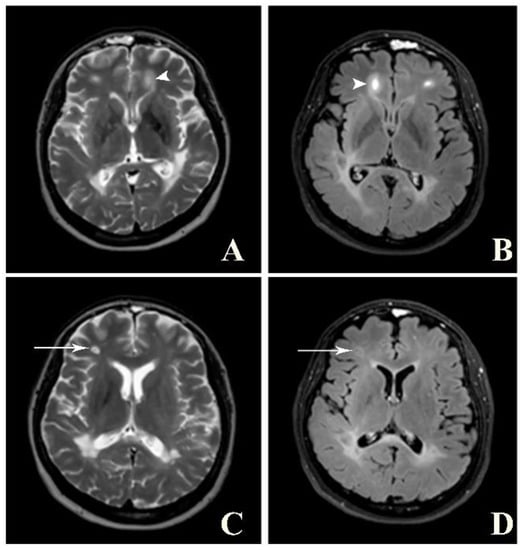

Figure 4.

Balo’s concentric sclerosis. A and B: Axial T2W (A) and post-contrast FLAIR (B) images show a few lesions with alternating band of high and low signal intensity at bilateral frontal lobes (arrowhead). C and D: Axial T2W (C) and post-contrast FLAIR (D) images of the same patient show faint central and peripheral enhancement at the right frontal lobe lesion (arrow).